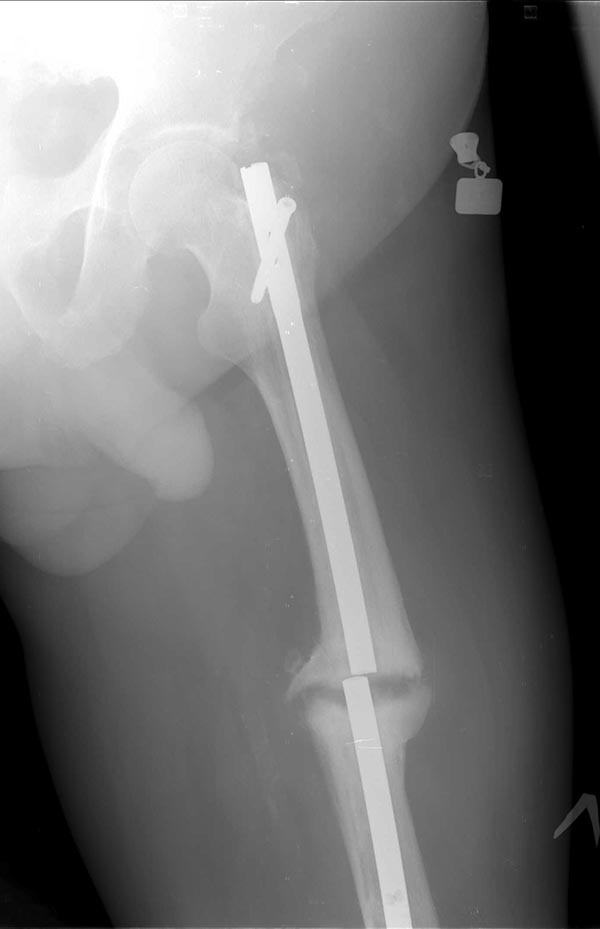

Коротко о пациенте: Возраст 60 лет, мужчина. Со слов травма в 2006 года-ДТП (сбит автомашиной) - в январе 2007 г. выполнено БИОС левого бедра , затем по неизвестным причинам в 2008 году реостеосинтез левого бедра штифтом ( снимков нет). Оперирован в одном из городов Сибири. Передвигался с тростью, с июля 2014 г. был вынужден встать на костыли в связи с усилением болей в области левого коленного сустава, левого бедра. В декабре 2014 г. боли в левом бедре усилились, появилась поталогическая подвижность.Сопутствующие заболевания:

На снимках( это снимки январь 2015г), которые выложил, определяется гипертрофический ложный сустав с/3 бедренной кости, перелом штифта на уровне перелома, штифт канюлированный.Состояние больного удовлетворительное, по анализам компенсирован.